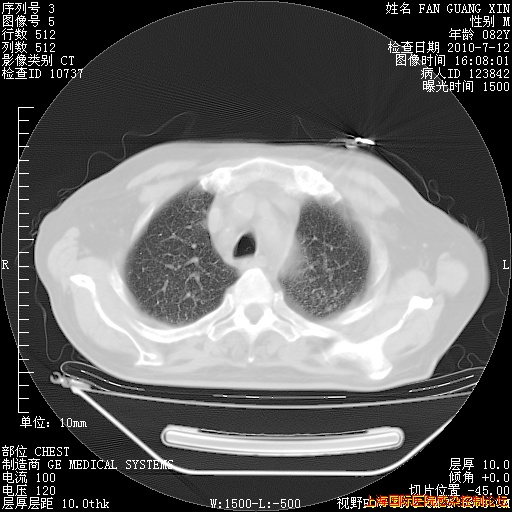

今天复查CT

今天CT

整整相隔30天的肺部CT好像有所好转啊。甲强龙减量第3天,需要观察体温。